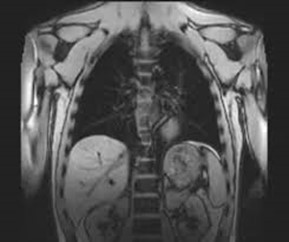

MRI scan of the body is mostly performed to evaluate:

• organs of the chest and abdomen—including the heart, liver, biliary tract, kidneys, spleen, bowel, pancreas, and adrenal glands.

• tumors of the chest, abdomen, or pelvis.